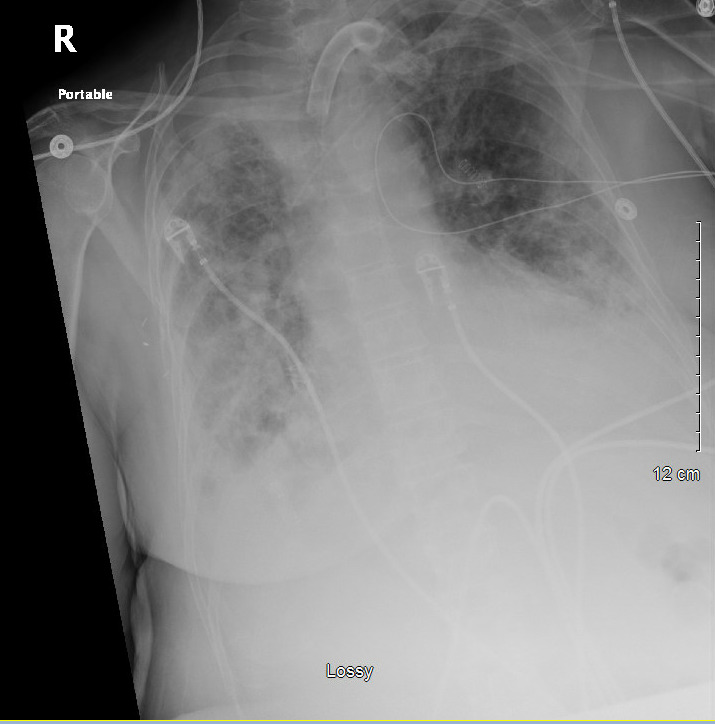

The patient’s condition began to decline again after 72 hours, as evidenced by elevations in WBC (peak 24.2 cells/μL), tempertaure (38.3°C), bandemia (10%), and persistent diffuse bilateral infiltrates on chest radiographs. (Image 2) Nafcillin was re-escalated to vancomycin and piperacillin-tazobactam, and pan cultures were performed. Sputum gram stain revealed gram-positive cocci (GPC), yeast, mold species, and gram-negative rods (GNR), and voriconazole was added. One of two blood cultures also showed GNR on gram stain. After no improvement in 48 hours, piperacillin-tazobactam was escalated to meropenem. The GPC again resulted MSSA, and vancomycin was de-escalated to nafcillin.